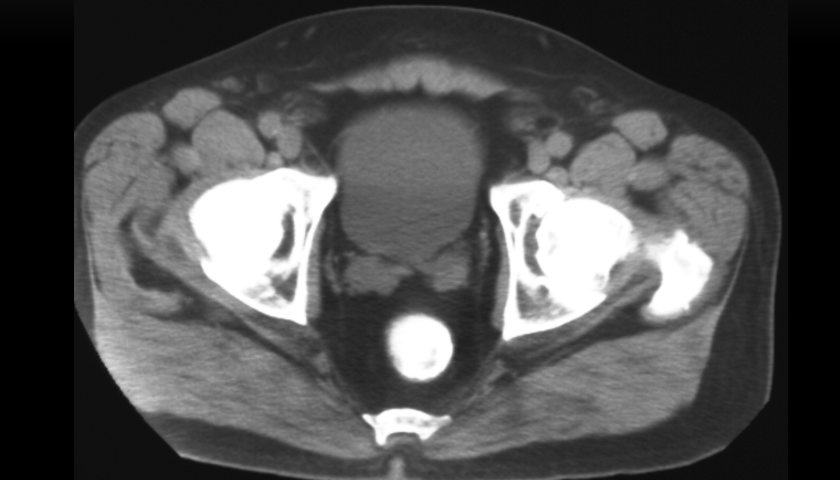

What type of imaging & view is this? And what abnormalities can we see

CT male pelvis, axial view

Calcification within the vascular structures; small bit of calcifications in vas deferes